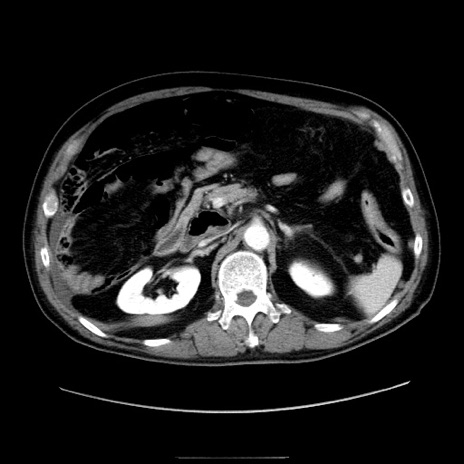

症例30(横断像)

【症例】80歳代男性

【現病歴】約6時間前から臍下部痛が出現。次第に腹部膨隆・背部痛も生じてきたため来院。背部痛の場所は変化しない。

【身体所見】意識清明、BT 36.3℃、BP  131/87mmHg、P 87bpm、SpO2 100%(RA)、臍周囲自発痛・圧痛あり、反跳痛なし、自発痛部位に一致して板状硬あり、腹部膨隆、腸雑音減弱、CVA tenderness両側陰性。

【データ】WBC 19600、CRP 0.33